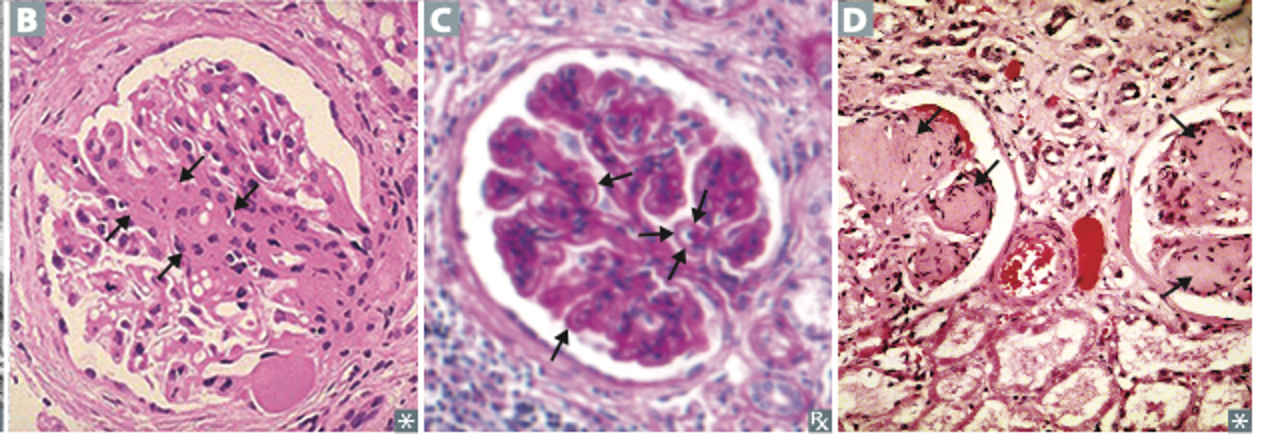

문제 1. 저는 현재 다양한 형태의 신장 질환, 특히 신증후군을 공부하고 있습니다. 이 병리의 발생을 예방하는 데 예방적 투석이 효과가 있을 가능성을 규명하기 위해 실험을 수행하고자 합니다. 저는 서로 다른 신증후군으로 진단된 환자들의 신장 생검에서 채취한 조직병리 표본을 분석하고 있습니다. 제시된 모든 샘플은 투석 치료 이전에 채취된 것입니다. 첨부된 이미지는 모두 광학 현미경(으로 촬영되었고, 헤마톡실린-에오신(H&E) 염색을 사용했습니다. 이미지를 바탕으로, 다음 진술 중 참인 것을 고르세요.

1. 이미지 B와 D는 분절성 사구체 경화가 보이며 Kimmelstiel–Wilson 병변은 없고, hyalinosis와 모세혈관 고리의 collapse가 동반되어 있다.

2. 이미지 C는 호산성 결절성 사구체경화가 보이고, mesangial matrix expansion과 세동맥의 hyaline 침착이 관찰되어 미세혈관 침범을 시사한다.

3. Bowman 주머니의 effacement가 이미지 C와 D에서 관찰된다.

4. 이미지 D에서 화살표가 가리키는 것은 세포외 기질 침착으로, 결절성 사구체경화를 시사한다.